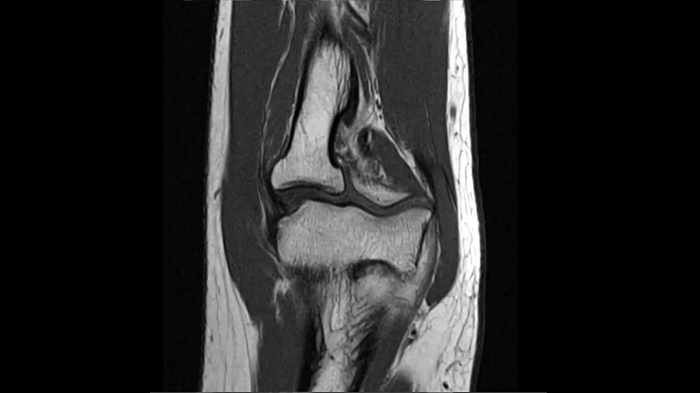

Elbow

T2 TSE with Deep Resolve

Exceptional performance for small joints owing to Deep Resolve.

Deep Resolve Gain & Sharp

0.3 x 0.3 x 3.0 mm2

TA 2:54 minutes

MAC-ID: 7aaaa0190. Image Credit: Siemens Healthineers

PD TSE Fat Sat with Deep Resolve

Thanks to Deep Resolve, outstanding performance for small joints is possible.

TA 3:43 minutes